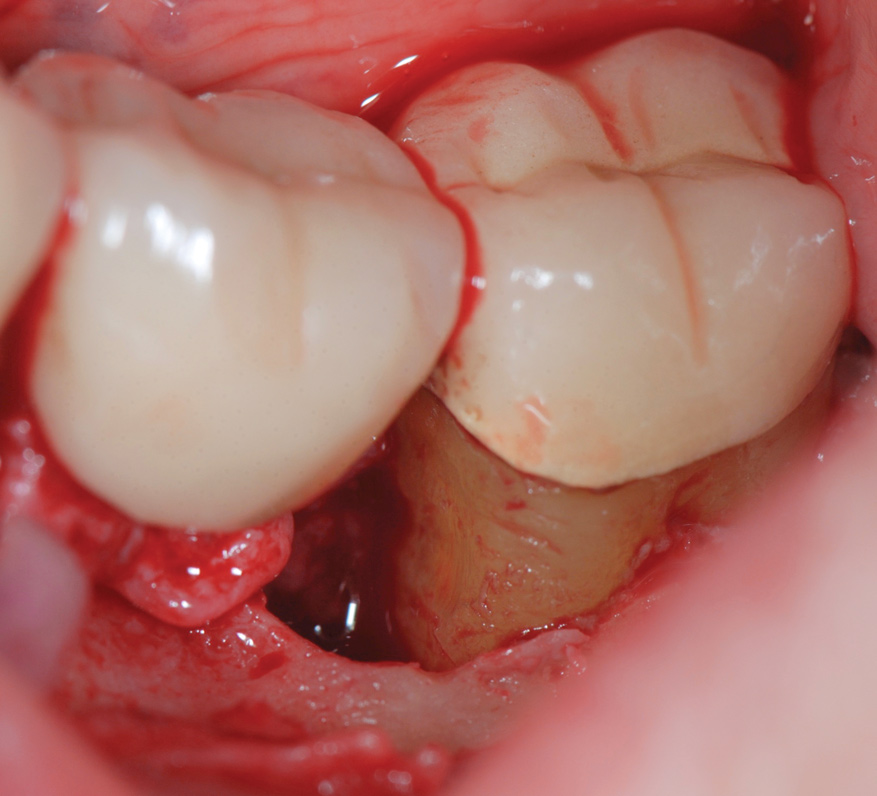

Regarding furcation defects, based on the available evidence, the AAP workshop concluded that regenerative therapy is a viable option to achieve predictable outcomes for their treatment in certain clinical scenarios.13 Periodontal regeneration has been established as a viable therapeutic option for the treatment of various furcation defects, including Class II defects, which represent a highly predictable scenario. The application of combined therapeutic approaches (ie, barrier, bone replacement graft with or without biologics) appears to offer an advantage over monotherapeutic algorithms.13 Figure 12 through Figure 15 depict the periodontal regenerative treatment of two previously restored teeth with intrabony and furcation defects using mineralized FDBA and EMD.

(12.) Pretreatment photograph of two previously restored teeth exhibiting gingival recession and probing depths equal to or greater than 15 mm.

Figure 12

(14.) Intrasurgical photograph of regenerative treatment with mineralized FDBA and EMD.

Figure 14